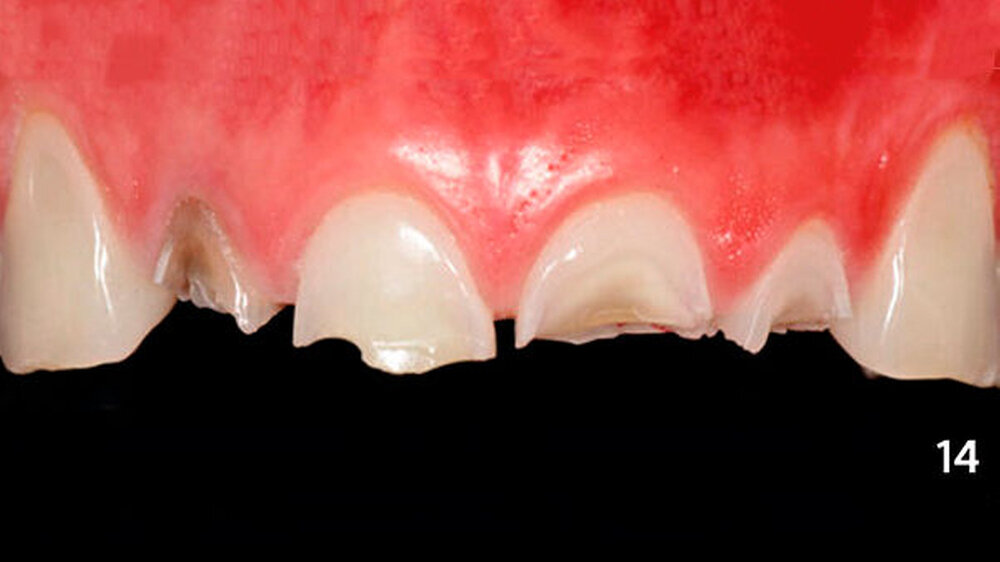

Nach der Bisshebung im Unterkiefer wurden die erosiven Frontzahndefekte im Oberkiefer ebenfalls mit Kompositadhäsiv versorgt (Abb. 14). Zunächst wurden die bukkalen Zahnhartsubstanzverluste freihändig mit Komposit aufgebaut (Abb. 15), und es wurde eine Alginatabformung genommen. Im zahntechnischen Labor wurden die inzisalen Anteile der Zähne aufgewachst, sodass anschließend ein Silikonschlüssel angefertigt werden konnte (Abb. 16).